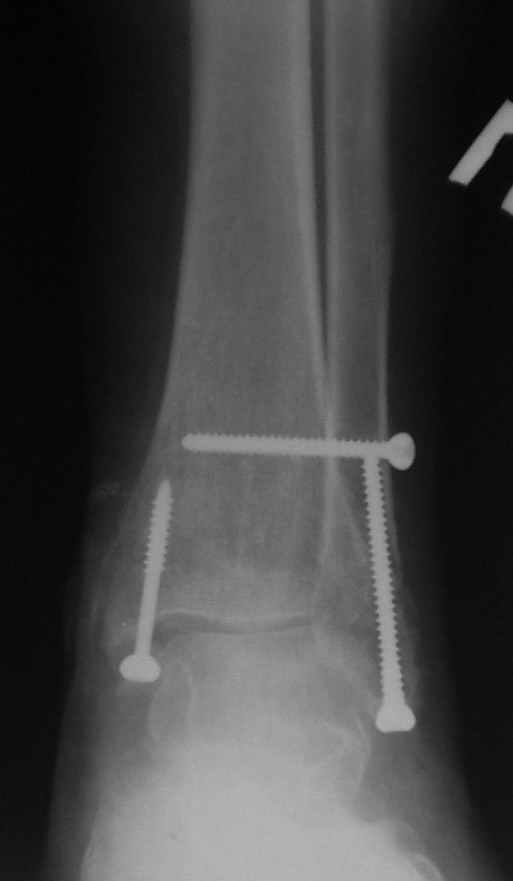

Ниже рентгенограммы

15 ноября прямой

15 ноября боковой

15 ноября трехчетвертной

12 января прямой

12 января боковой

12 января трехчетвертной

Риторический вопрос - в каком руководстве рекомендован такой способ остеосинтеза наружной лодыжки?

Очевидно, такой результат операции был запрограммирован. При невосстановленной длине и практически нефиксированной малоберцовой кости (этот кортикальный винт - как карандаш в стакане), при неустраненном подвывихе, невправленной и тоже нефиксированной внутренней лодыжке нет стабильной вилки сустава. Если такую операцию сделать даже сразу, а не через 4 месяца, то результат ожидаем

тот же.

Вариант с артродезом уже обсудили. Хотя, после увиденых снимков, пессимизм насчет восстановительной операции у меня, например, несколько уменьшился. Особенного уж какого-то остеопороза не видно даже на январских снимках. Можно черед мини-доступы убрать винты, аппаратом вправить малоберцовую кость, устранить подвывих стопы. Ну а дальше фиксировать малоберцовую пластиной сзади. А может, и напряженной Y-спицей попробовать - Анатолий Федорович, как Вы полагаете? Внутреннюю - то, что осталось, если уже не получится сделать спицами и проволокой, то что-то типа пластики дельтовидной связки. А может, и не трогать ее вовсе... В общем, выбор непростой,

Если до сих ничего не сделано, с артродезом сустава в данный момент я бы повременил, на выставленных январских снимках хорошо сохранившийся сустав, а в "мортиз" (трехчетвертной) и на боковых снимках не менее 5 мм укорочение малоберцовой кости. Косые переломы лучше фиксировать пластинами, как то мы разбирали случай, где было отмечено, что это закон "таранная кость всегда следует за малоберцовой".

Делались ли сравнительные снимки, оба сустава в фас на одной пленке? Если с них сделать скиаграммы и наложить их, будет видно, удалось ли устранить наружный подвывих стопы.

Вообще-то начинать надо бы с восстановления длины малоберцовой кости. Вряд ли возможно сделать первой репозицию внутренней лодыжки точно, в таком сроке местных ориентиров нет. Соответственно, смещение внутренней лодыжки кнаружи только уменьшается, но не ликвидируется полностью. Тогда и таран из наружного подвывиха не удается полностью вывести.

тарнная кость находится в латеральном подвывихе, что снижает шансы этого сустава.

Это видно по снимку - середина суставной поверхности тарана должна быть против середины суставной поверхности тибии. Причины, что это не так:

1. Внутренняя лодыжка не на месте

2. наружная лодыжка укорочена

3. Возможно есть компрессионный перелом наружной части пилона тибии.

В подобных случаях лучше всего начинать с главной цели - вправить таран, временно зафиксировать спицами и используя таран как шаблон поставить на место лодыжки, неважно в какой последовательности.